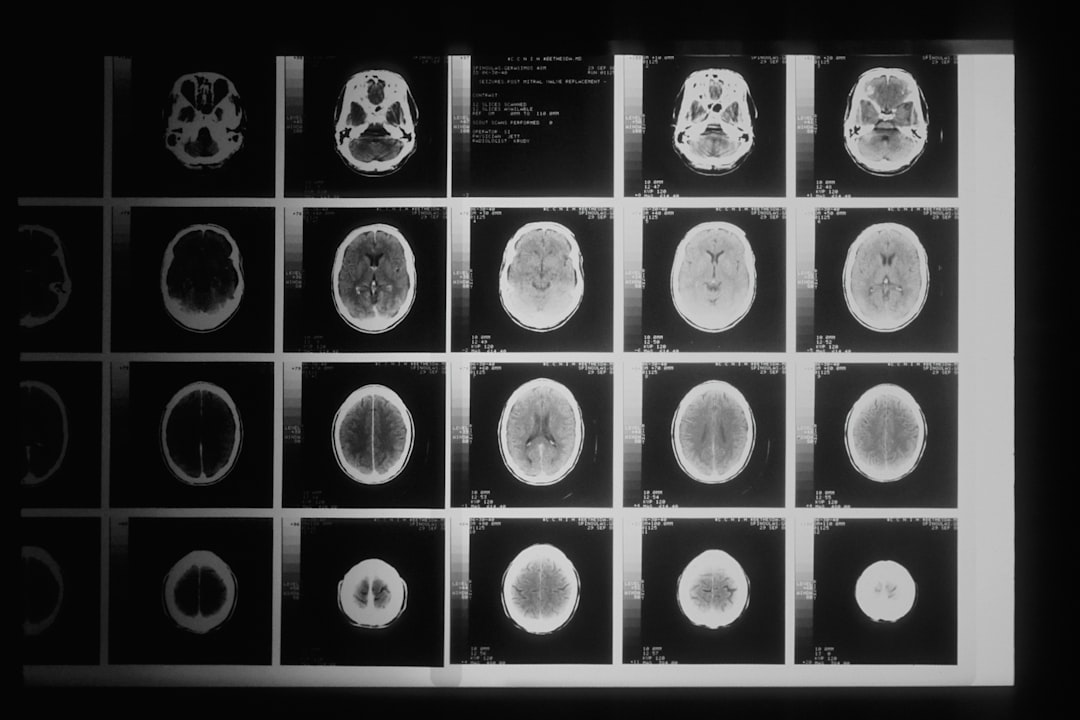

손발저림 증상을 검사하기 위해서는 다양한 방법이 있습니다. 일반적으로는 의료진이 환자의 증상과 병력을 청취한 후, 신경전도검사나 근전도검사를 진행합니다. 이러한 검사들은 손발의 신경 기능을 점검하고, 문제의 원인을 파악하기 위한 기초 자료를 제공합니다. 청주시 손발저림 증상 검사 가능한 신경과 병원에서는 이러한 검사가 체계적으로 이루어집니다.

신경전도검사는 전극을 통해 신경 신호의 전도를 측정하여, 신경의 상태를 평가하는 방법입니다. 이를 통해 신경이 제대로 작동하고 있는지 확인할 수 있으며, 증상의 원인에 대한 단서를 제공합니다. 또한, 근전도검사는 근육의 전기적 활동을 확인하여, 신경이나 근육에서 발생할 수 있는 문제를 진단합니다. 이러한 모든 과정은 전문의의 철저한 관리 하에 진행됩니다.